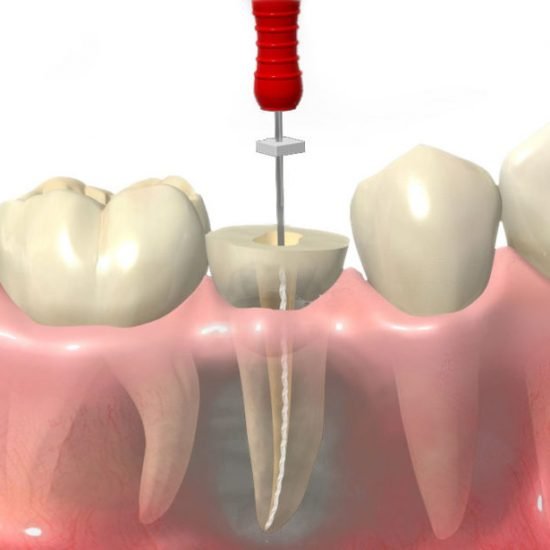

Quando parliamo di Endodonzia san giorgio a cremano intendiamo le procedure eseguite per sagomare, detergere e sigillare i canali radicolari (situati all’interno delle radici dei denti) dove è contenuta la polpa dentaria.

Nel suo complesso la terapia canalare endodontica viene spesso definita “Devitalizzazione di un dente”, usando questo termine per definire la rimozione del “nervo” in un dente che fa male.

Le fasi della devitalizzazione sono:

- Accesso alla camera pulpare

- Accesso ai canali radicolari

- Otturazione con materiale termoplastico

- Controllo radiografico